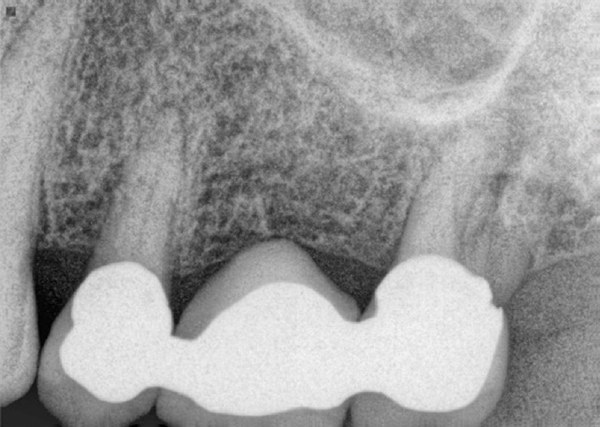

Sinus Expansion Due To Missing Teeth Advanced Periodontics Implant Dentistry

Lifting Low Sinuses For Dental Implant Treatment